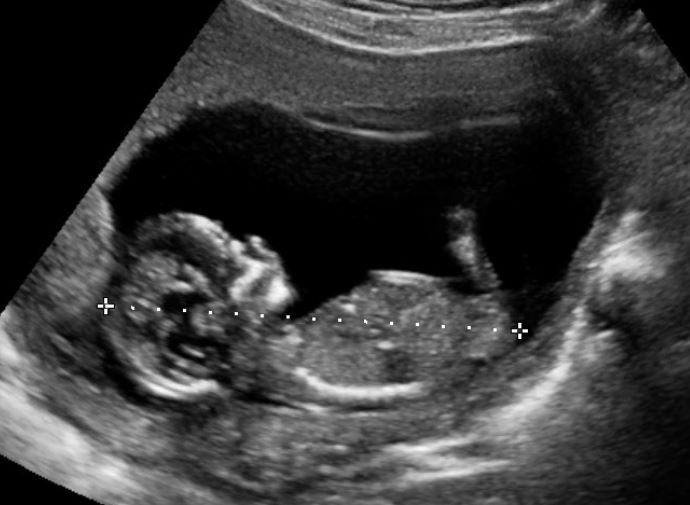

I'm guessing girl, long nub and pretty flat despite that slight flick at the end - a friend had one just like that and was confirmed girl x

It looks very girly and 13 weeks is more accurate. Good luck!

Great to know, thanks :0) You are dead right - it looks flat but the fork section goes up. Hence why I am sitting on the fence.